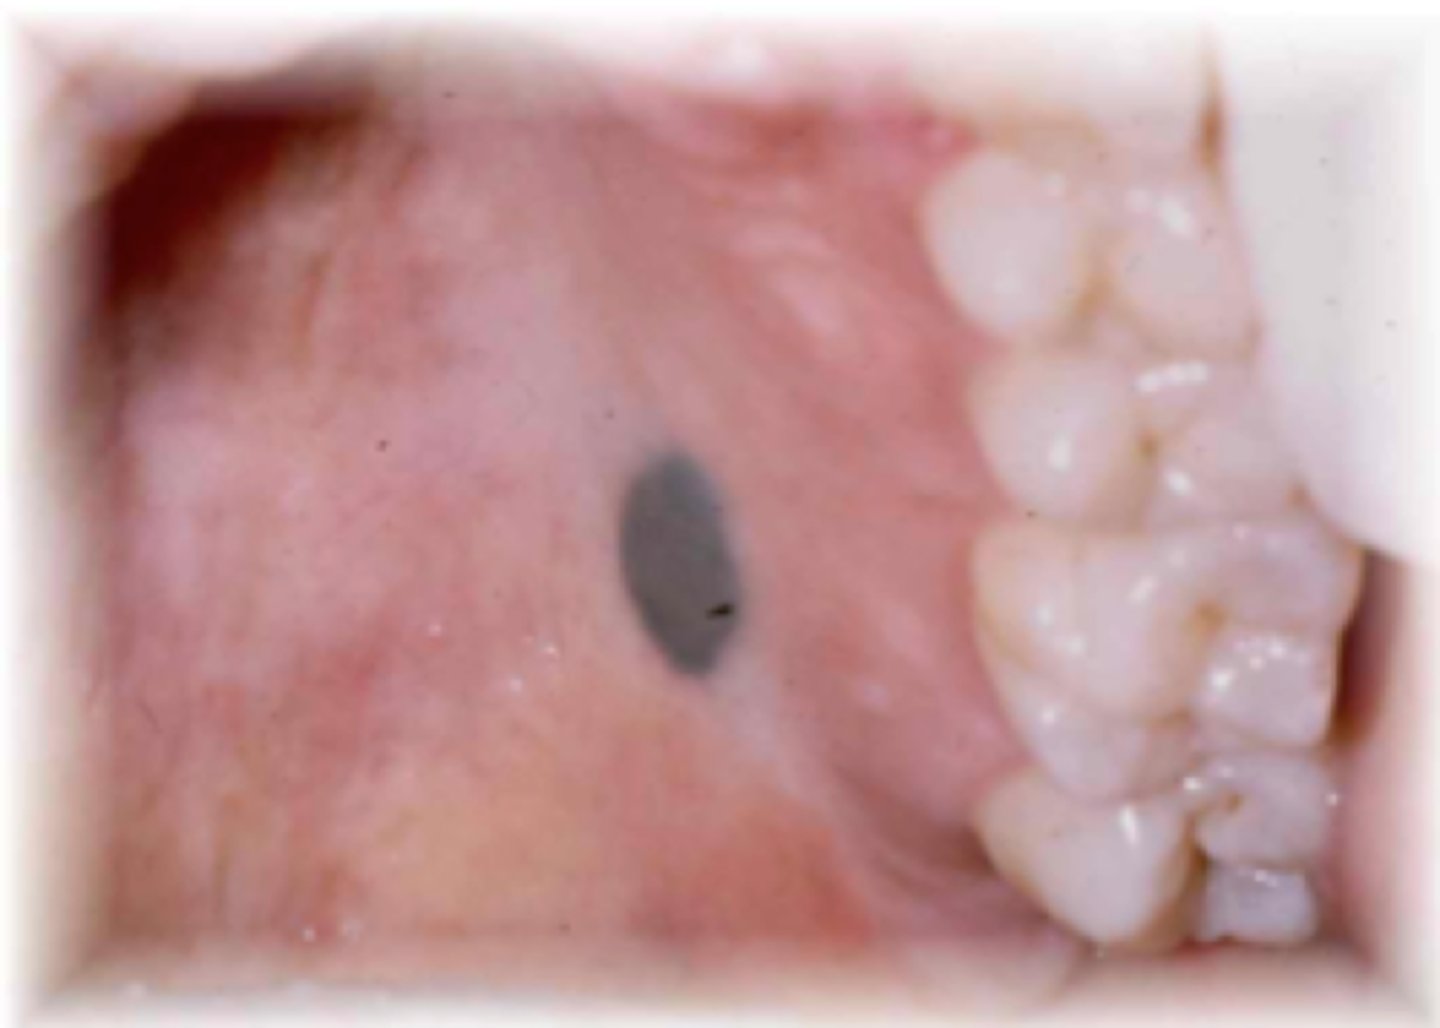

What is a melanocytic nevus?

well-defined, single, brown-black macule

⢠rare intraorally

⢠proliferation of melanocytes

⢠uniform color

⢠less than 6mm

⢠aka MOLE